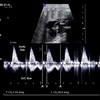

15

Q

What pathology?

A

See UV pulsations